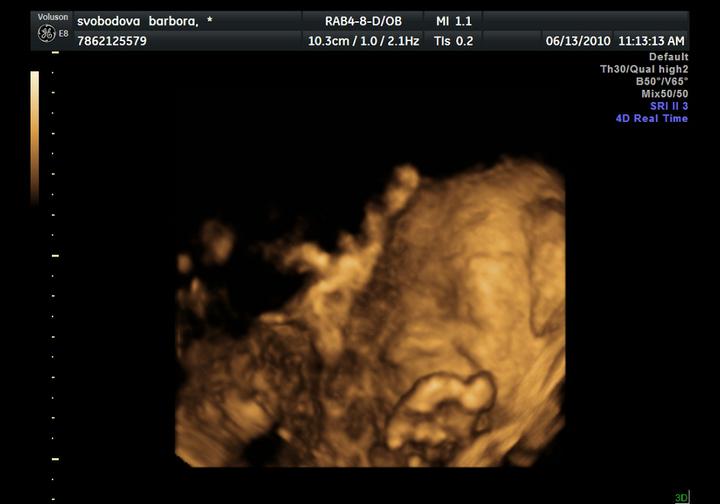

dneska jsme byli na velkém UZ, Adámek potvrzen a máme 414 g a asi 20 cm, odpovídáme 21+4, krásně rosteme 🙂